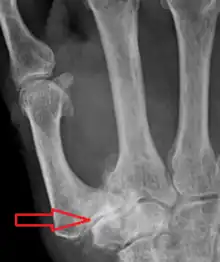

Diagnosis

TMC OA is diagnosed based on symptoms and signs.[8] Radiographs can confirm the diagnosis and the severity of TMC OA. Other diagnoses in this region include scaphotrapezial trapezoid arthritis and first dorsal compartment tendinopathy (De Quervain syndrome) although these are usually easy to distinguish.

Classification

TMC OA severity was classified by Eaton and Littler which can be simplified as follows:[21][22]

Stage 1:

Stage 2:

Stage 3:

Stage 4:

A simpler classification is no arthritis, some arthritis, and severe arthritis.[23] This simpler classification system omits the potentially contradictory details of the Eaton/Littler classification and keeps scaphotrapezial arthrosis separate.